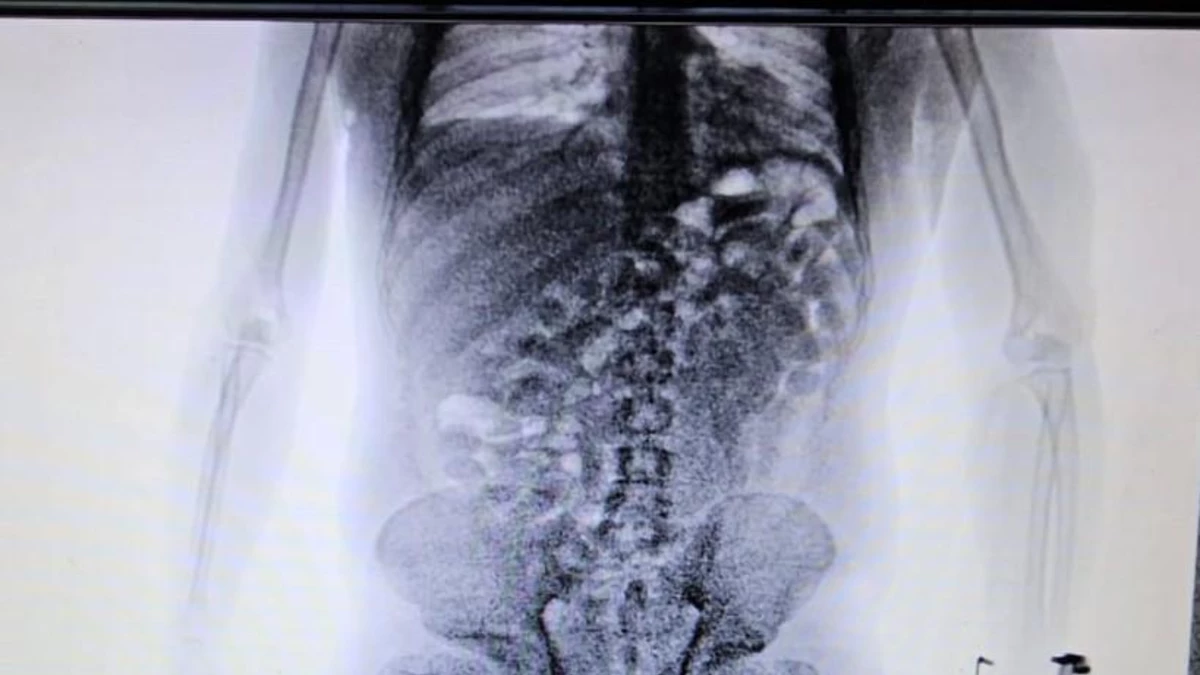

Policiales Una mujer embarazada protagonizó un impactante accidente: el auto lo conducía su esposo y ambos fueron hospitalizados